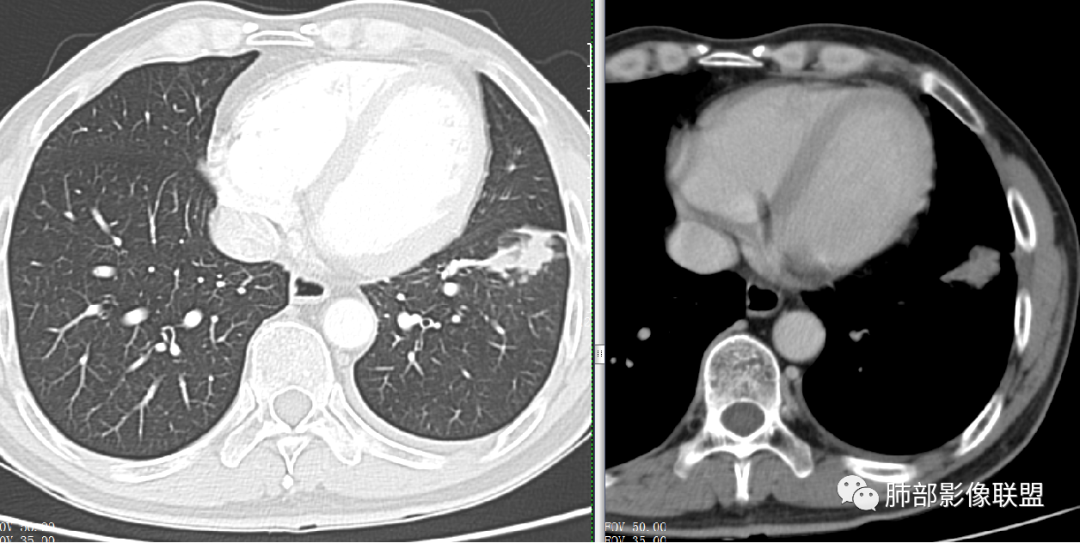

良性的依据有五点:

第一,周围收缩,凹陷,桃尖,边缘大部分平直,周围卫星灶。

第二,栽脏不明确,

第三,强化有环形强化的感觉,坏死区太圆太规整。

第四,有支气管爬行的感觉。

第五,专门提出三个月前胸片多发小结节,三个月后变大成肿块。

尘缘:

对于这种良恶性征像都有,而且缺乏一锤定音的依据的病例,更多还是要常规分析,找出线索及关联性,临床处理要良性结节恶性对待,先按良性结节抗炎治疗同时,查结核隐球相关指标,短期内积极进行穿刺明确。